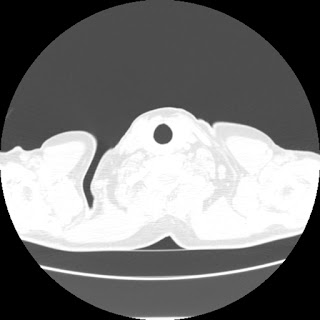

A 62 years old man with enlarged mole on chest since 2 months.

CT chest :-